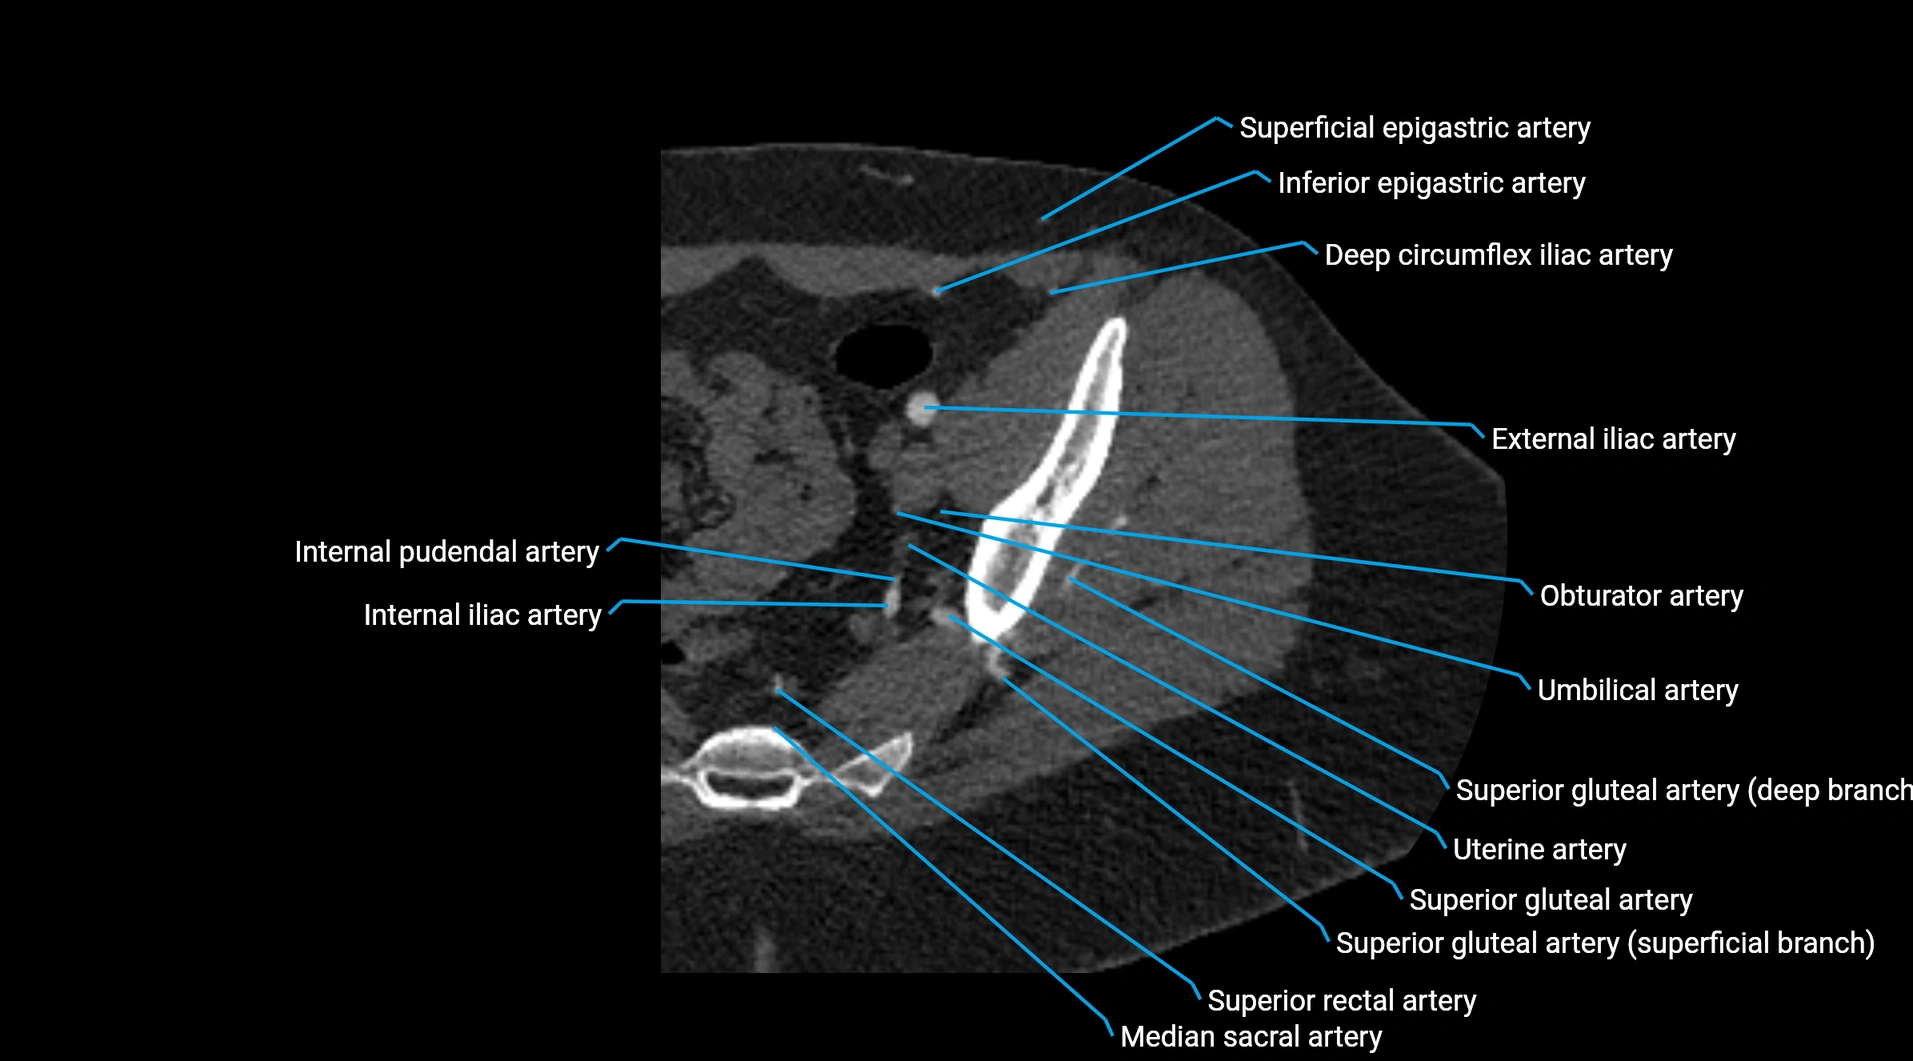

CT images

image